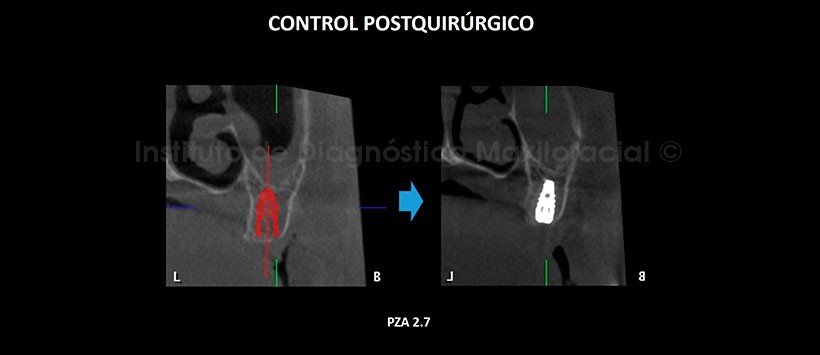

En la tomografía computarizada de haz cónico (TCHC), se realiza la planificación virtual de colocación de cuatro implantes dentales en zonas de piezas 17, 23, 26 y 27 (Figura 2, 3), y sobre la planificación se realiza la confección virtual de la guía quirúrgica (Figura 4). En la reconstrucción 3D (Figuras 5) se aprecia con detalle la orientación y la disposición final de los implantes dentales a ser colocados, además se observa la guía quirúrgica confeccionada virtualmente que posteriormente fue impresa físicamente para su utilización en el procedimiento quirúrgico (Figura 6).

En la tomografía de control post quirúrgico (Figura 7, 8, 9, 10 y 11), se aprecia los implantes con estructura ósea circundante, en las posiciones donde fueron planificadas virtualmente.